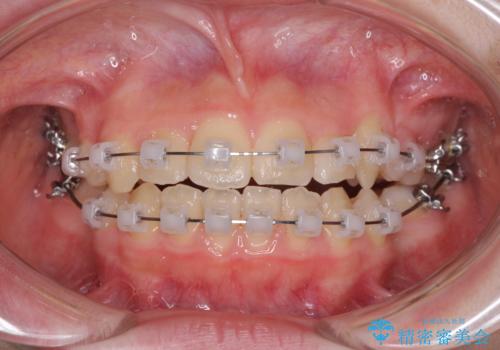

- クリアブラケット

下顎の乳歯は永久歯と比べて幅が大きいため、抜歯した場合のスペースが大きく、治療には長期間を要することが一般的です。

今回の患者様は中学生ということもあり、成人の患者様と比べ動きが速く、2年間で治療を終えることができました。